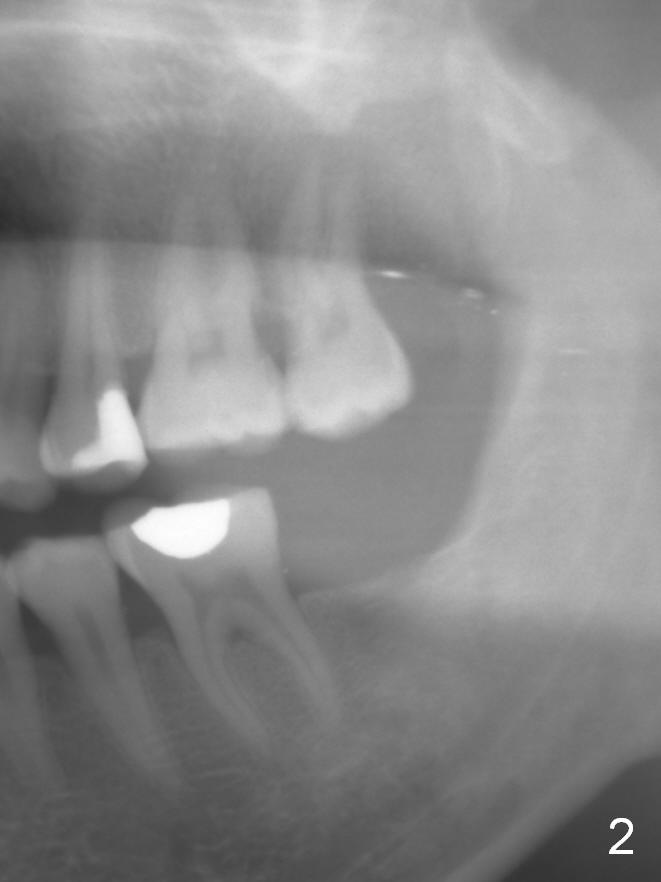

In fact, the tooth 15 had basically no extrusion 6 years earlier (Fig.2) with even occlusal plane. When the tooth is intruded orthodontically, the occlusal plane may be not even (Fig.3). When the implant at #18 osteointegrates (Fig.4 green), fabricate a provisional (grey rectangle) with higher mesial occlusal surface. For certain period of time, the tooth #15 may change its axis so that the mesial portion of the tooth may be intruded more (Fig.5 arrow).